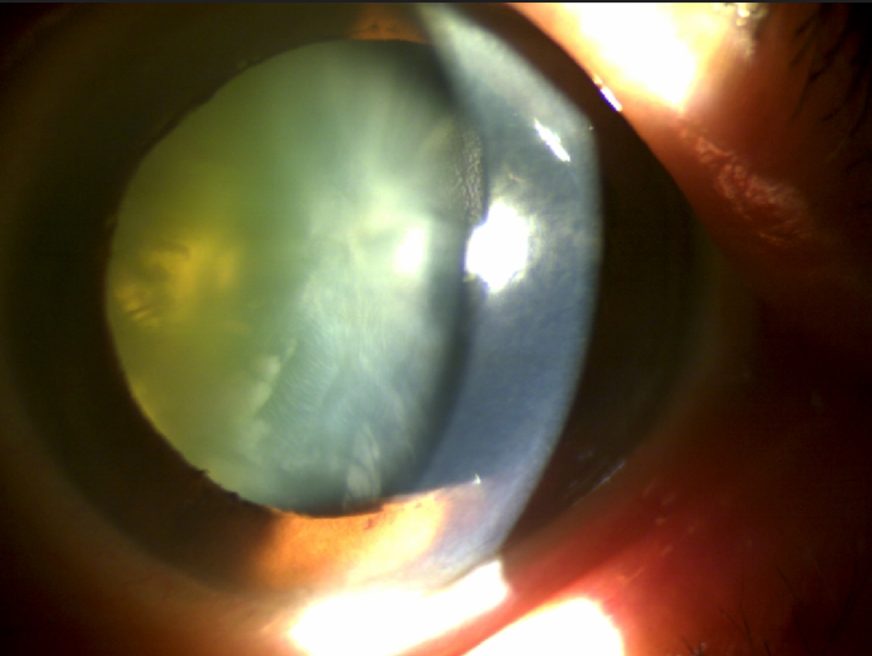

인공수정체 탈구 : 칸나브라바 공막고정수술

54세 남성 환자 사례

수술 8개월 후 나안시력 0.9

54세 남성 환자 사례

수술 8개월 후 나안시력 0.9

수술 전

수술 후

※ 해당 이미지는 본원에서 직접 촬영한 사진입니다.